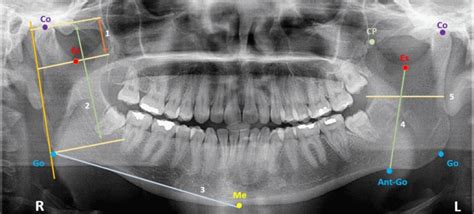

La mandíbula se compone de:

- Cuerpo mandibular: La parte horizontal que forma la barbilla.

- Ramas mandibulares: Las dos extensiones verticales que se proyectan hacia arriba desde el cuerpo.

El foramen mandibular es una estructura crucial en la cara interna de la rama mandibular. A partir de este orificio, el conducto mandibular se dirige oblicuamente en el espesor del hueso en dirección caudal y ventral. Luego, incurvándose, sigue paralelamente a aproximadamente 1 cm de la base de la mandíbula hasta acercarse al foramen mentoniano.

La mandíbula presenta una escotadura sigmoidea, que es una depresión en el borde superior de la rama mandibular. Se halla excavado en forma de canal.